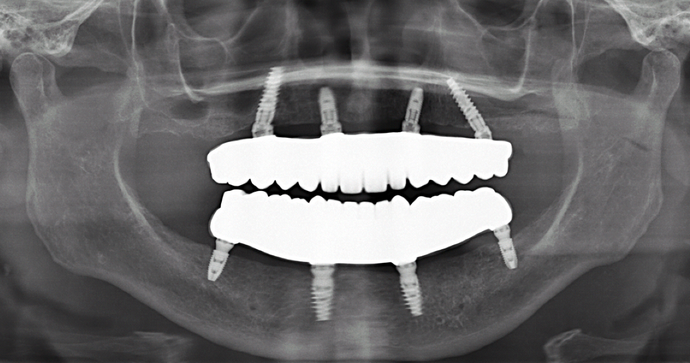

Patient had severe gum disease and she started losing her teeth one by one and was very unhappy with her partials. Patient was holding on to the very last few teeth in her mouth which were loose, in order to avoid wearing dentures! When she discovered Dr Bidra, and was informed that she could get transformed in one single day, she and her husband were immediately motivated. Patient had her teeth extracted, implants placed and new teeth installed all in one day.

Procedures : extractions, implants, All on 4 , Teeth in a day, no bone grafting and full mouth reconstruction with monolithic zirconia bridges.